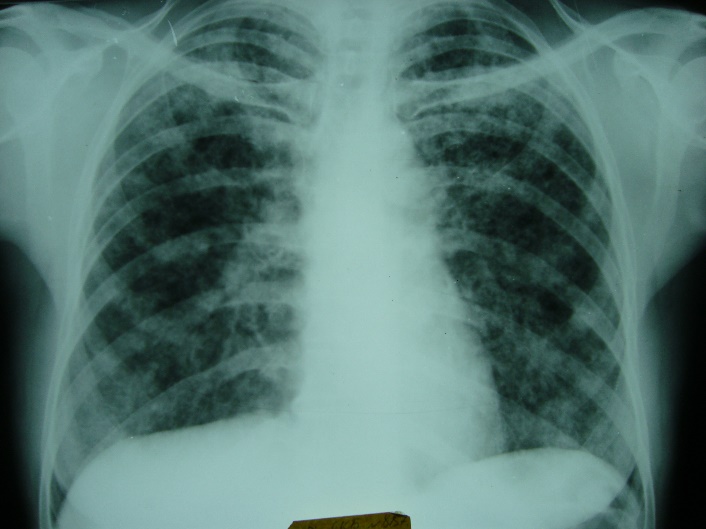

Какой патологический процесс в легких вы видите// диссеминированный туберкулез легких// саркоидоз легких// +метастазы в легкие// альвеококкоз легких// эхинококкоз легких